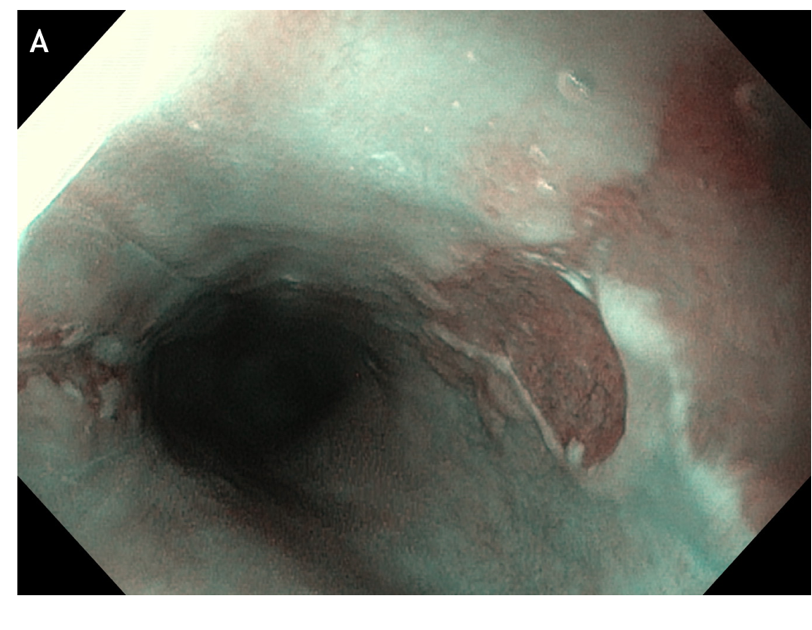

Figure 4 Multiple small focal areas round in shape of gastric tissue, one of them slightly raised, noted in the right lateral field, 10 cm from the incisors, in a young man presenting for unexplained upper dysphagia.